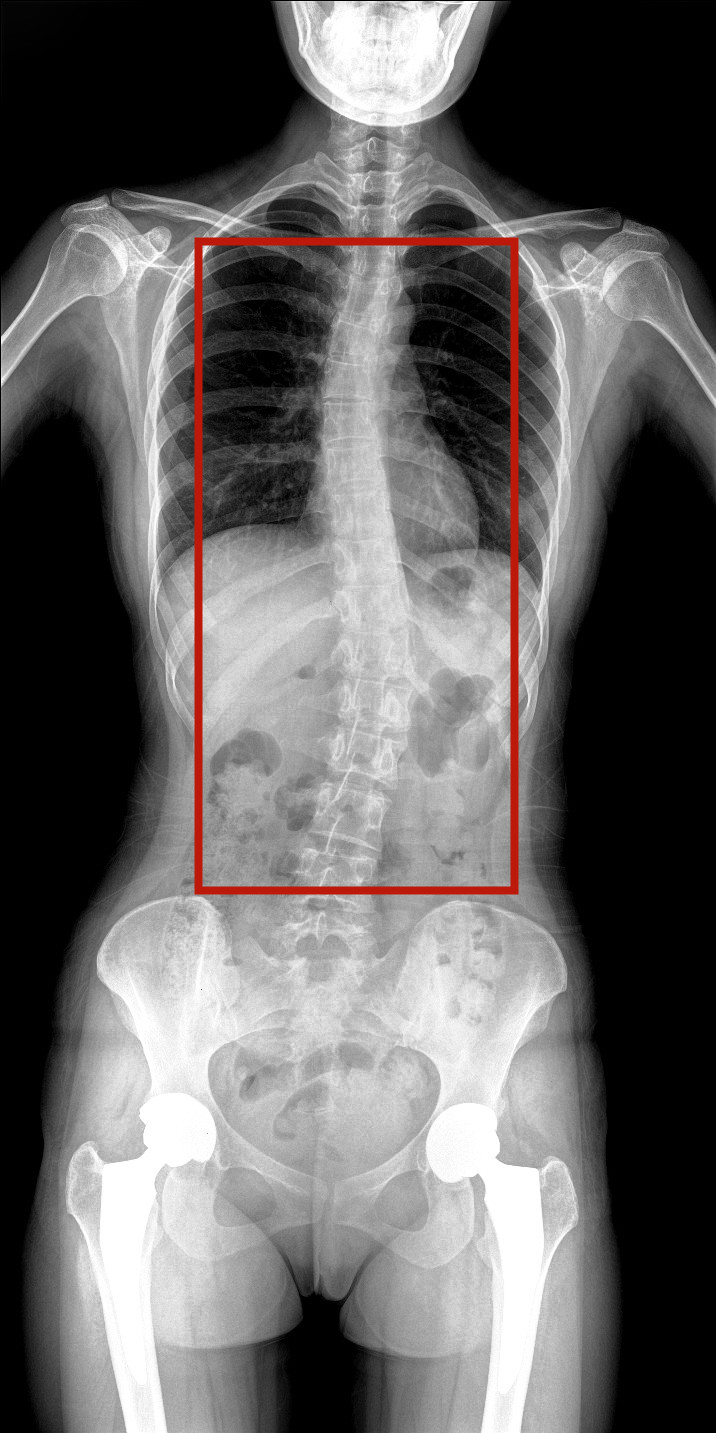

病情描述:患者,女,23歲,免疫系統畸變導致的脊柱側彎

虛線框示患者脊柱側彎明顯

脊柱圖像范圍包含脊椎、雙側肩部及骨盆。片內頸椎、胸椎、腰椎、骶椎、雙肩及骨盆重組影像結構清晰,對比度高,對位、對線好,接緣區無重疊、遺漏、縫隙。能夠滿足臨床測量脊柱Cobb角及臨床人體平衡線等指標的測量,整體上能對全脊柱進行觀察診斷。